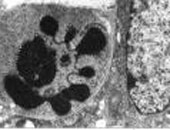

Andreas Villunger vom Institut für Pathophysiologie und seine Kooperationspartner in Melbourne konnten nachweisen, dass zwei Proteine, die den Zelltod fördern, eine wesentliche Rolle bei der Behandlung gewisser Tumore spielen. Sie erhoffen sich dadurch neue Erkenntnisse für die Krebsbehandlung. Ihre Ergebnisse wurden im Science veröffentlicht.

In der soeben unter dem Titel "p-53 and Drug-Induced Apoptotic Responses Mediated by BH3-Only Proteins Puma and Noxa" erschienenen Arbeit in der Fachzeitschrift Science konnte das Forscherteam gemeinsam mit Kooperationspartnern in Melbourne zeigen, dass zwei zelltod-fördernde Proteine der Bcl-2 Familie (genannt PUMA/bbc3 und NOXA) kritisch für die apoptotische Wirkung von gängigen Zytostatika und der Strahlenbehandlung sind. Lymphozyten und Fibroblasten von Mäusen, denen diese Proteine fehlen, zeigen eine drastisch verringerte Sensitivität gegenüber Gammastrahlung, Zytostatika- aber auch Steroidbehandlung. Es wäre somit denkbar, dass das Fehlen dieser Proteine mit einem schlechten Ansprechen von gewissen Tumoren auf Behandlung korreliert. Die Wissenschaftler überlegen daher, ob diese Proteine als prognostische Marker herangezogen werden können. Weiters wäre es denkbar, dass das Fehlen dieser Protein die Entstehung von bösartigen Erkrankungen erleichtern, beschleunigen oder gar erst ermöglichen könnte - eine Theorie, die die Wissenschaftler als nächsten Schritt überprüfen werden.(sp)